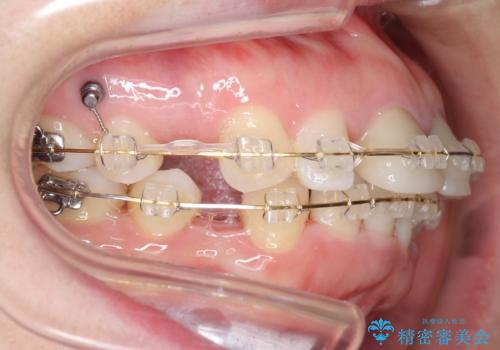

治療途中

矯正治療前に、一旦、引っ込めた前歯の角度を元に戻してから(出っ歯の仮歯をもう一度つけました・・・!)矯正しました。